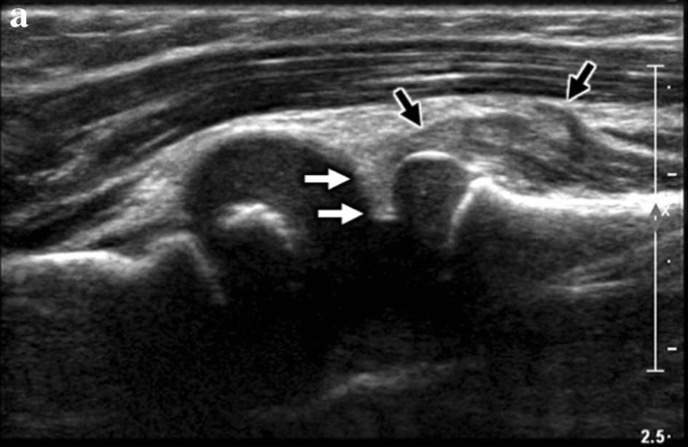

RESULTATS

A. US longitudinale à travers l'articulation radiocapitellaire montre:

- ligament annulaire échogène interposé entre l'articulation radiocapitellaire (flèches blanches)

- muscle supinateur élargi et hétérogène (flèche noire) qui est positionné proximalement

La combinaison de ces résultats a été décrite comme un « signe J » ou un « signe crochet »